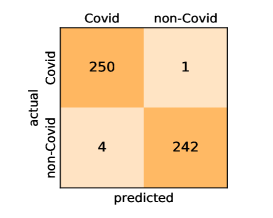

Here, we present and discuss the obtained results for detecting COVID-19 on the considered CT image datasets with different deep networks. We report the quantitative results along with the confusion matrices for every single architecture of the adopted networks.

On the SARS-CoV-2 CT dataset, ResNet101 achieves the best overall performance with respect to almost all evaluation metrics, with an average accuracy and F1-score of and , respectively. The model also achieves an average sensitivity rate of indicating that, on average, only two COVID-19 images are falsely predicted as negatives. It is also powerful enough to correctly identify all Non-COVID-19 cases with only one false positive resulting a specificity rate of . The highest sensitivity score of is achieved by the InceptionV3 model, where only one COVID-19 image is falsely predicted as negative on average. The SqueezeNet model obtains the lowest performance with respect to all evaluation metrics with a fairly acceptable average accuracy and sensitivity scores of and , respectively. Also the ShuffleNet architecture obtains satisfactory performance with approximately improvements on average for all metrics compared with SqueezeNet. Although the results obtained by these models are inferior compared with the rest of models, but they are more efficient. This matches their main objective of reducing the computational costs rather than improving their visual recognition abilities. The rest of models achieve competitive performance and very promising results with slight performance differences. Comparing the different variants of ResNet and DenseNet, we can see that the deeper variants from each architecture yield a slightly better performance. The deeper ResNet101 and ResNeXt101 show a marginal gain in performance compared with their shallower counterparts. The details about class-wise results for each model are summarized in the confusion matrices in Figure 9.

Our models achieve fairly good performance compared with the recently published work using the exact network architectures. This can bet attributed to a better optimization of our models and the effectiveness of our fine-tuning strategy using custom-sized inputs determined specifically for each architecture. Here, we see that DenseNet201 outperforms all other architectures. The model achieves average accuracy and sensitivity scores of and , respectively. It also identifies all COVID-19 images with only four images, on the average, are falsely predicted as Non-COVID-19. DenseNet169 achieves the second best average accuracy of and a very high sensitivity identical to the best model. The DenseNet121 and Xception models have nearly identical results for all evaluation metrics. We observe that small-sized networks such as ResNet18 achieves comparable results with other deeper models. The SqueezeNet and ShuffleNet models perform at a similar level of accuracy. The variants of the ResNeXt models have comparable results and perform as good as the different ResNet variants. A detailed analysis on the class-wise results for individual models is presented in the confusion matrices in Figure 10.